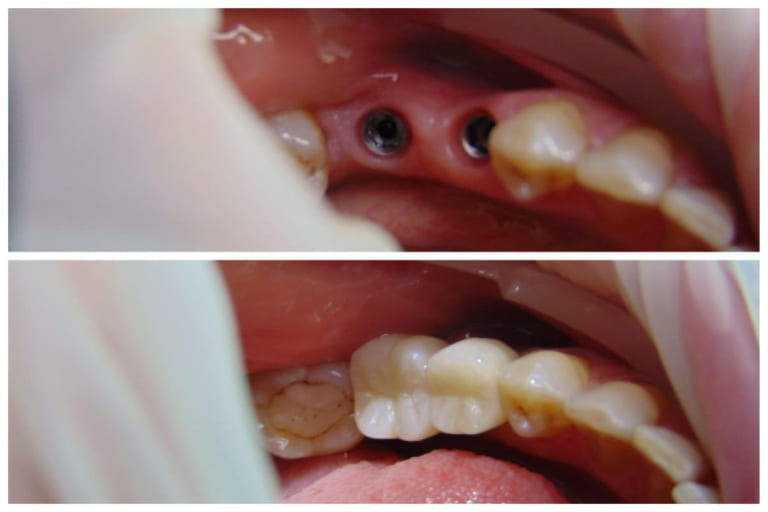

Установка двух имплантов и двух коронок

Цель визита пациента

- Пациентка Марина обратилась в нашу клинику с жалобами на отсутствие зубов в области 35, 46 зз

Детали лечебного процесса

- После КТ исследования были установлены 2 имплантата. С последующей установкой керамических коронок

Продолжительность и этапы лечения

- 2 месяца

- 3 визита